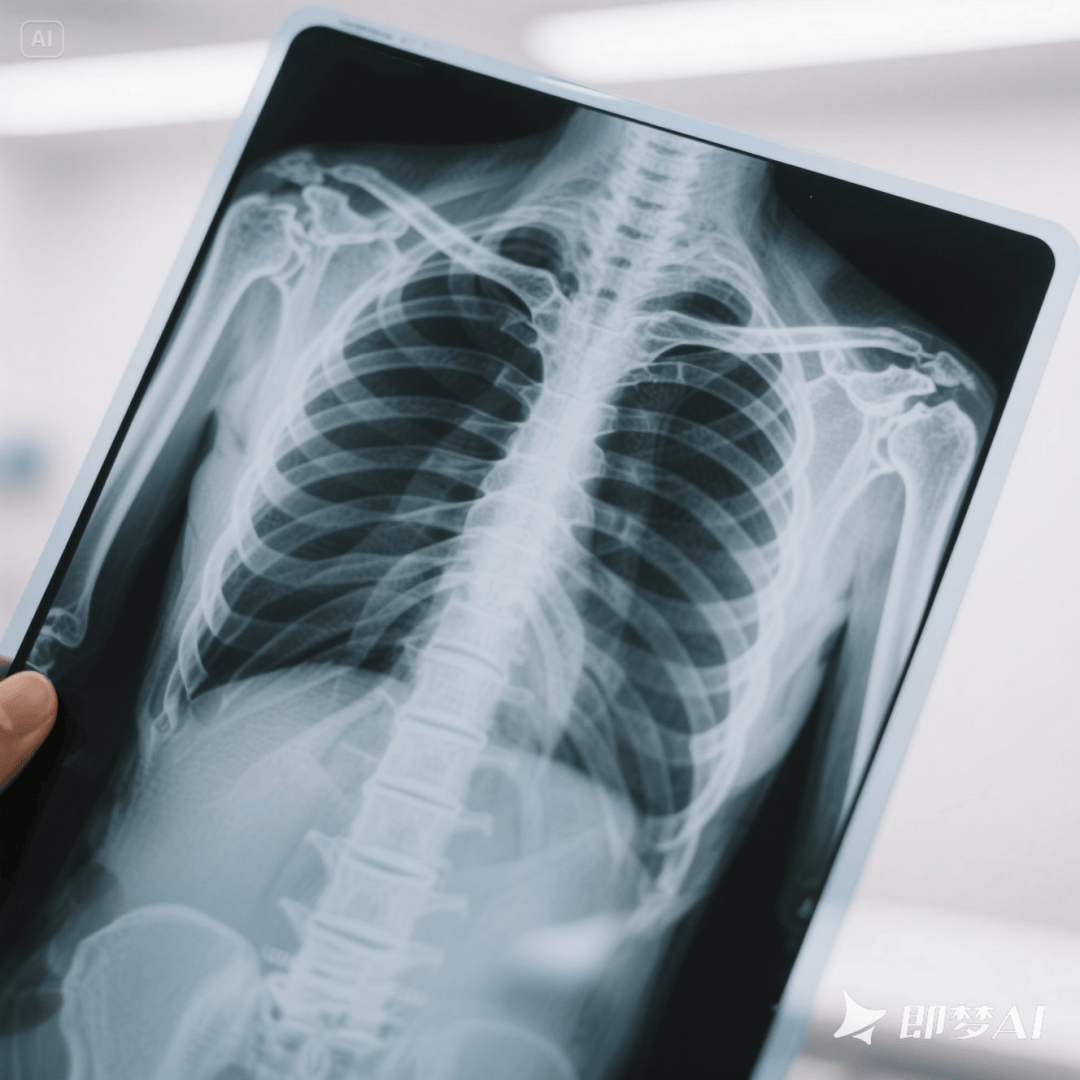

完全性内脏反位,也就是通常所说的“镜面人”“镜子人”或“镜像人”,是一种罕见的先天性畸形。

“镜面人”的心脏、肝脏、脾脏、胆等器官的位置与正常人相反,心脏、脾脏在右边(正常在左边),肝脏位于左边(正常在右边)。心、肝、脾胃等器官位置左右对调,犹如镜中影像。

一般来说,“镜面人”虽然内脏全部错位,但只是位置发生变化,相互间的关系并未改变,因此 生理功能与正常人一样,对健康与生活都没有太大影响。

但是并不是所有内脏反位的患者都没有症状。有些患者患有先天性心脏病,比如大血管转位。还有一部分患有原发性纤毛运动障碍(PCD)的肺部疾病,这种疾病会导致肺部分泌物粘液堆积,从而导致支气管炎和鼻窦炎。